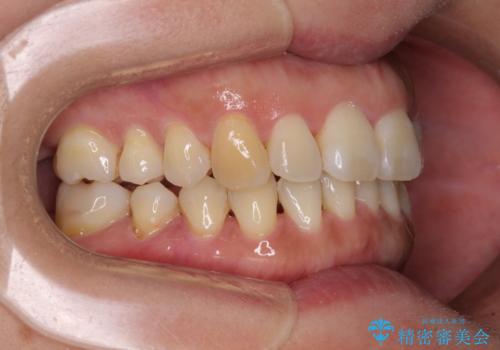

軽度な歯列不正 インビザライン・ライトによる矯正治療

- 上下前歯の叢生を気にして来院された患者様です。

費用を抑え、期間もあまりかけずに治療をしたいとのことで、インビザライン・ライトを用いて矯正治療を行うこととしました。